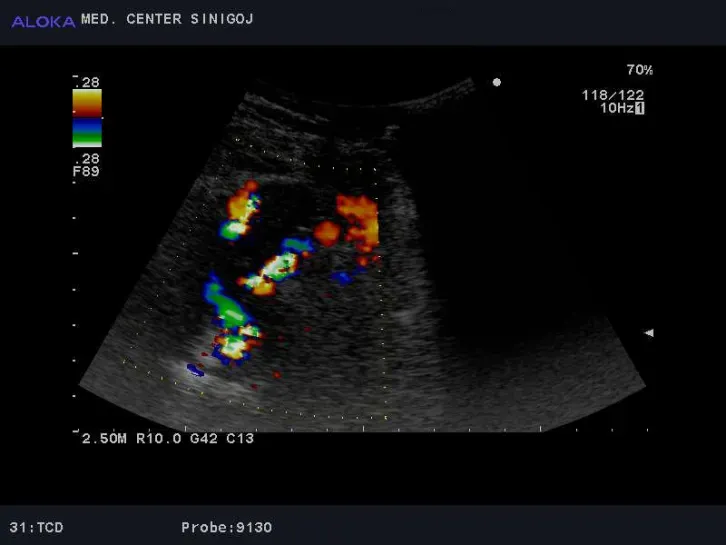

Predstavitev ultrazvoka možganskih arterij (BTCD)

Z ultrazvokom preiskujemo naslednje žile:

• arteria cerebri anterior - ACA

• arteria cerebri media - MCA

• arteria cerebri posterior - PCA

• arteria oftalmica - OA

• arteria basilaris - BA

• arteria vertebralis - VA